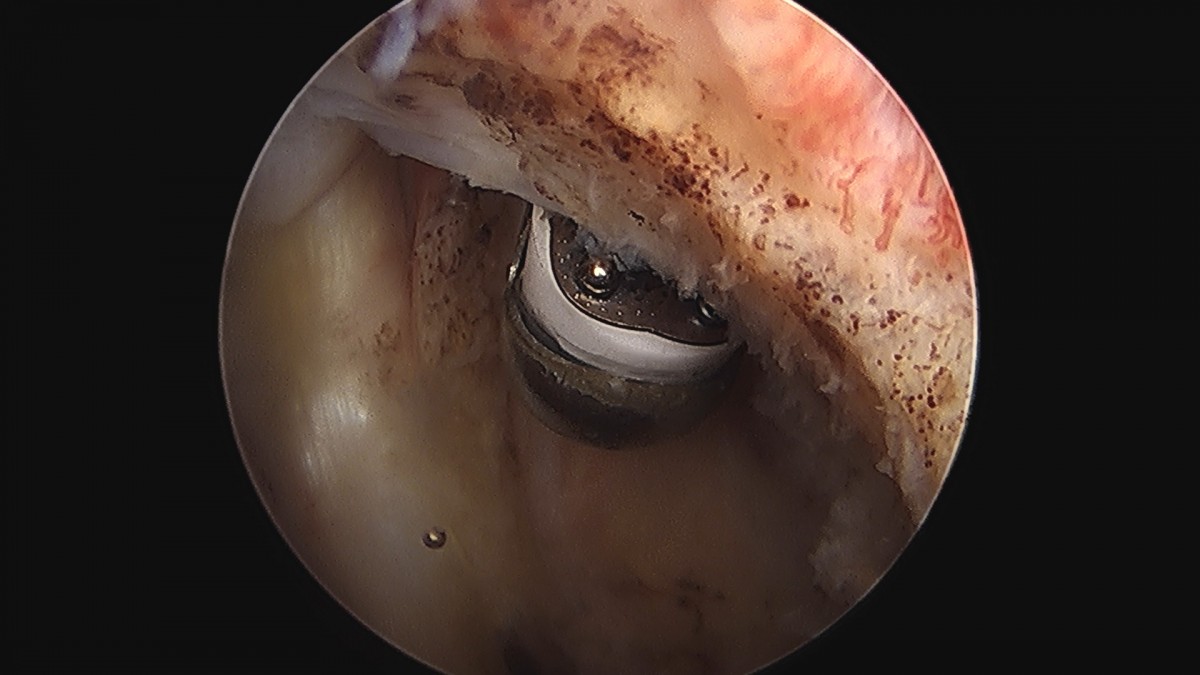

이재상원장님 어깨 견봉하 감압술 김봉O 환자

작성자 최고관리자 댓글 0건 조회 811회 작성일 25-09-16 15:28